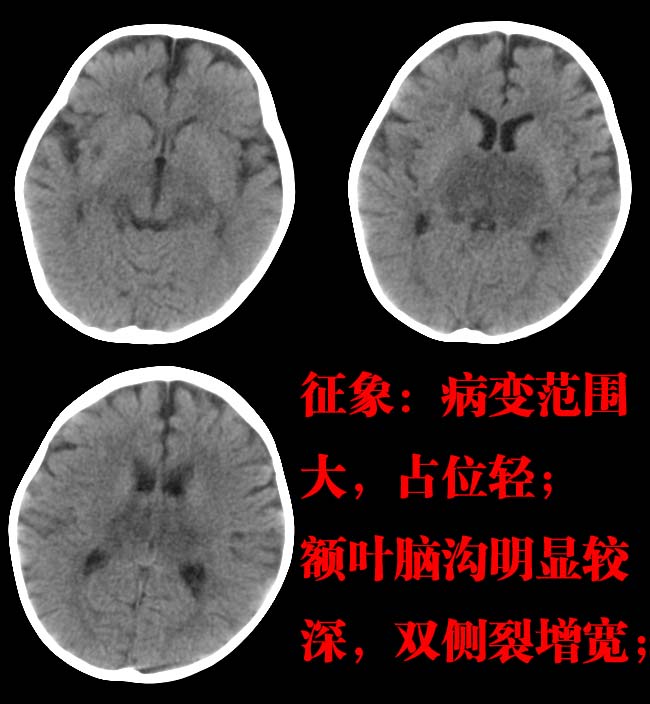

直接征象:双侧丘脑对称性密度减低;

1皮层区脑萎缩2丘脑区低密度考虑脑炎。